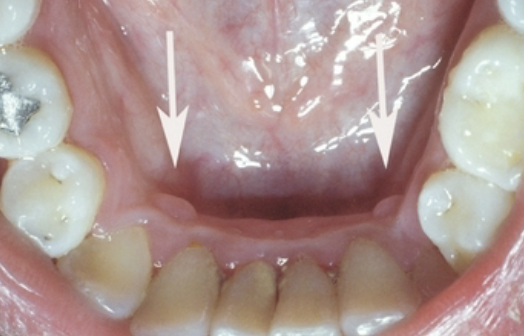

outgrowths of normal dense bone found on the lingual aspect of the mandible premolars are

mandibular tori